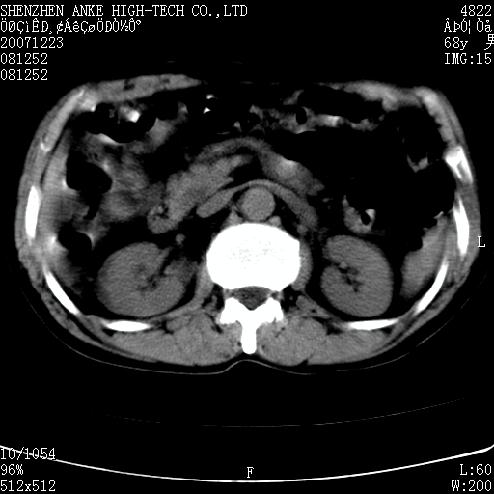

患者:男,63岁,2年前胆囊切除术后,现右上腹部剧烈疼痛近2天.

有无外伤史?右肾包膜下血肿可疑。

主要是问右肾有没有问题?患者无明显外伤史.

未见异常,病人差闭气,伪影较多.

肠管积气明显.

肠道准备不好,干扰影大。

肠道气体伪影干扰太大了,应该是干扰所致,未见明显异常。

肠道准备不好,胃底后壁显示不清,右肾改变考虑为伪影。